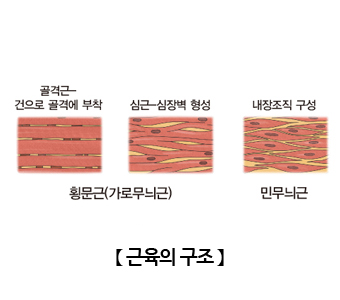

우리 몸의 골격을 이루는 뼈에 부착하여 운동을 가능하게 해주는 기관입니다. 우리 몸의 근육은 크게 골격근, 심장근, 내장근으로 구분할 수 있으며 기능에 따라 자신의 의사로 수축을 조절할 수 있는 수의근과 수축을 조절할 수 없는 불수의근, 모양에 따라 가로무늬근과 민무늬근으로 나눌 수 있습니다.

골격근

뼈에 붙어서 운동을 할 수 있게 해주는 근육으로 우리 몸의 근육 조직의 대부분을 차지합니다. 골격근은 가로무늬근육이며 수의근입니다. 골격근육은 수많은 근섬유로 구성되어 있습니다. 근섬유는 가늘고 긴 원기둥 모양의 세포로서 여러개의 핵과 근육수축에 필요한 에너지를 생산하는 미토콘드리아를 가지고 있습니다. 근섬유는 실모양의 구조물인 근원섬유로 되어있으며, 근원섬유는 근필라멘트로 이루어져 있습니다. 근필라멘트에는 액틴과 마이오신이 있어 근육수축에 관여합니다. 이들은 모두 다발 형태를 띄고 있습니다.

내장근

우리 몸의 소화기 내부 장기들의 벽을 구성하고 있는 근육으로 민무늬근육이며 자율신경에 의해 조절되기 때문에 불수의근입니다.

심장근

심장에서만 볼수 있는 근육으로 구조로는 골격근과 같이 가로무늬근이지만 기능으로 보면 자율신경에 의해 조절되는 불수의근으로 골격근육과 내장근육의 특징을 다 가지고 있는 근육입니다.